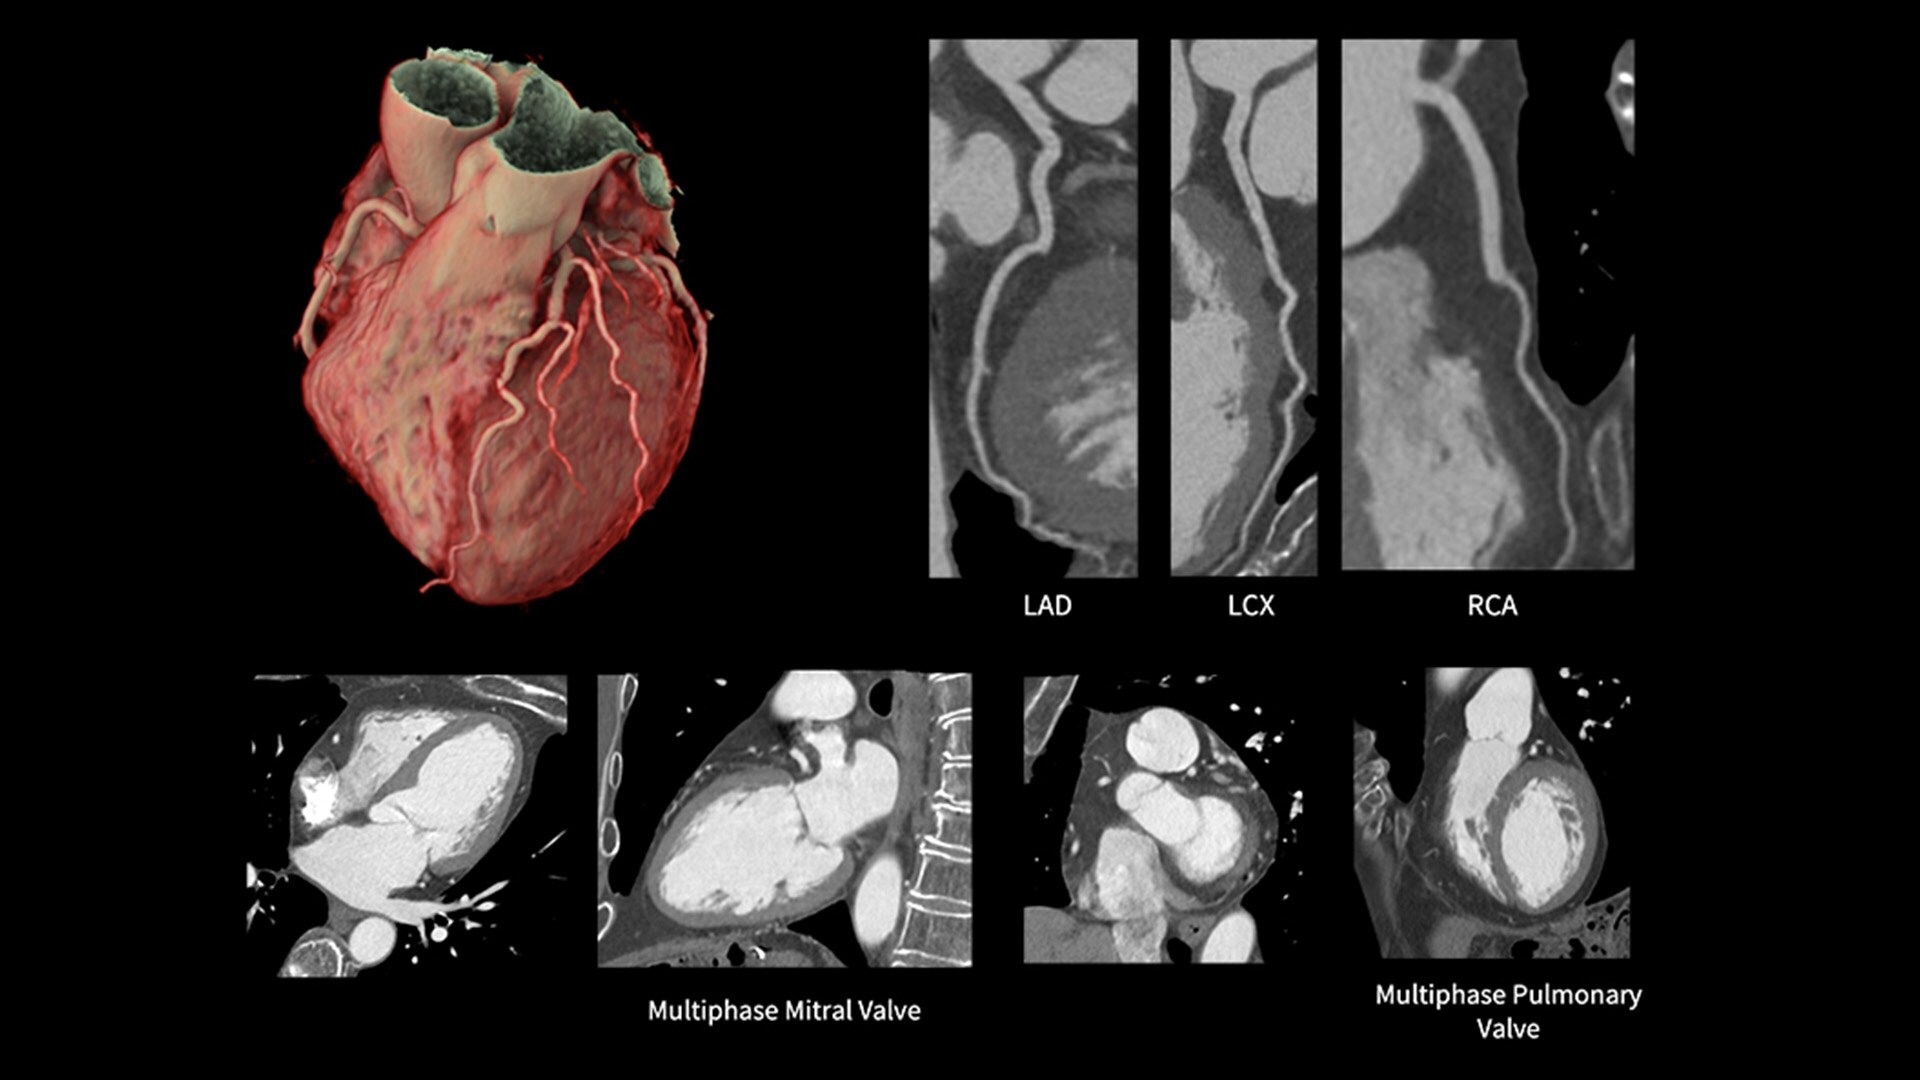

The ECG-less CT (a cardiac CT scan without an ECG trace) is an industry-first

Increases Cardiac CT access

Address cardiac exams where patient access and speed need to be prioritized

Simplified workflow

Useful in exams where excluding ECG traces would streamline patient preparation